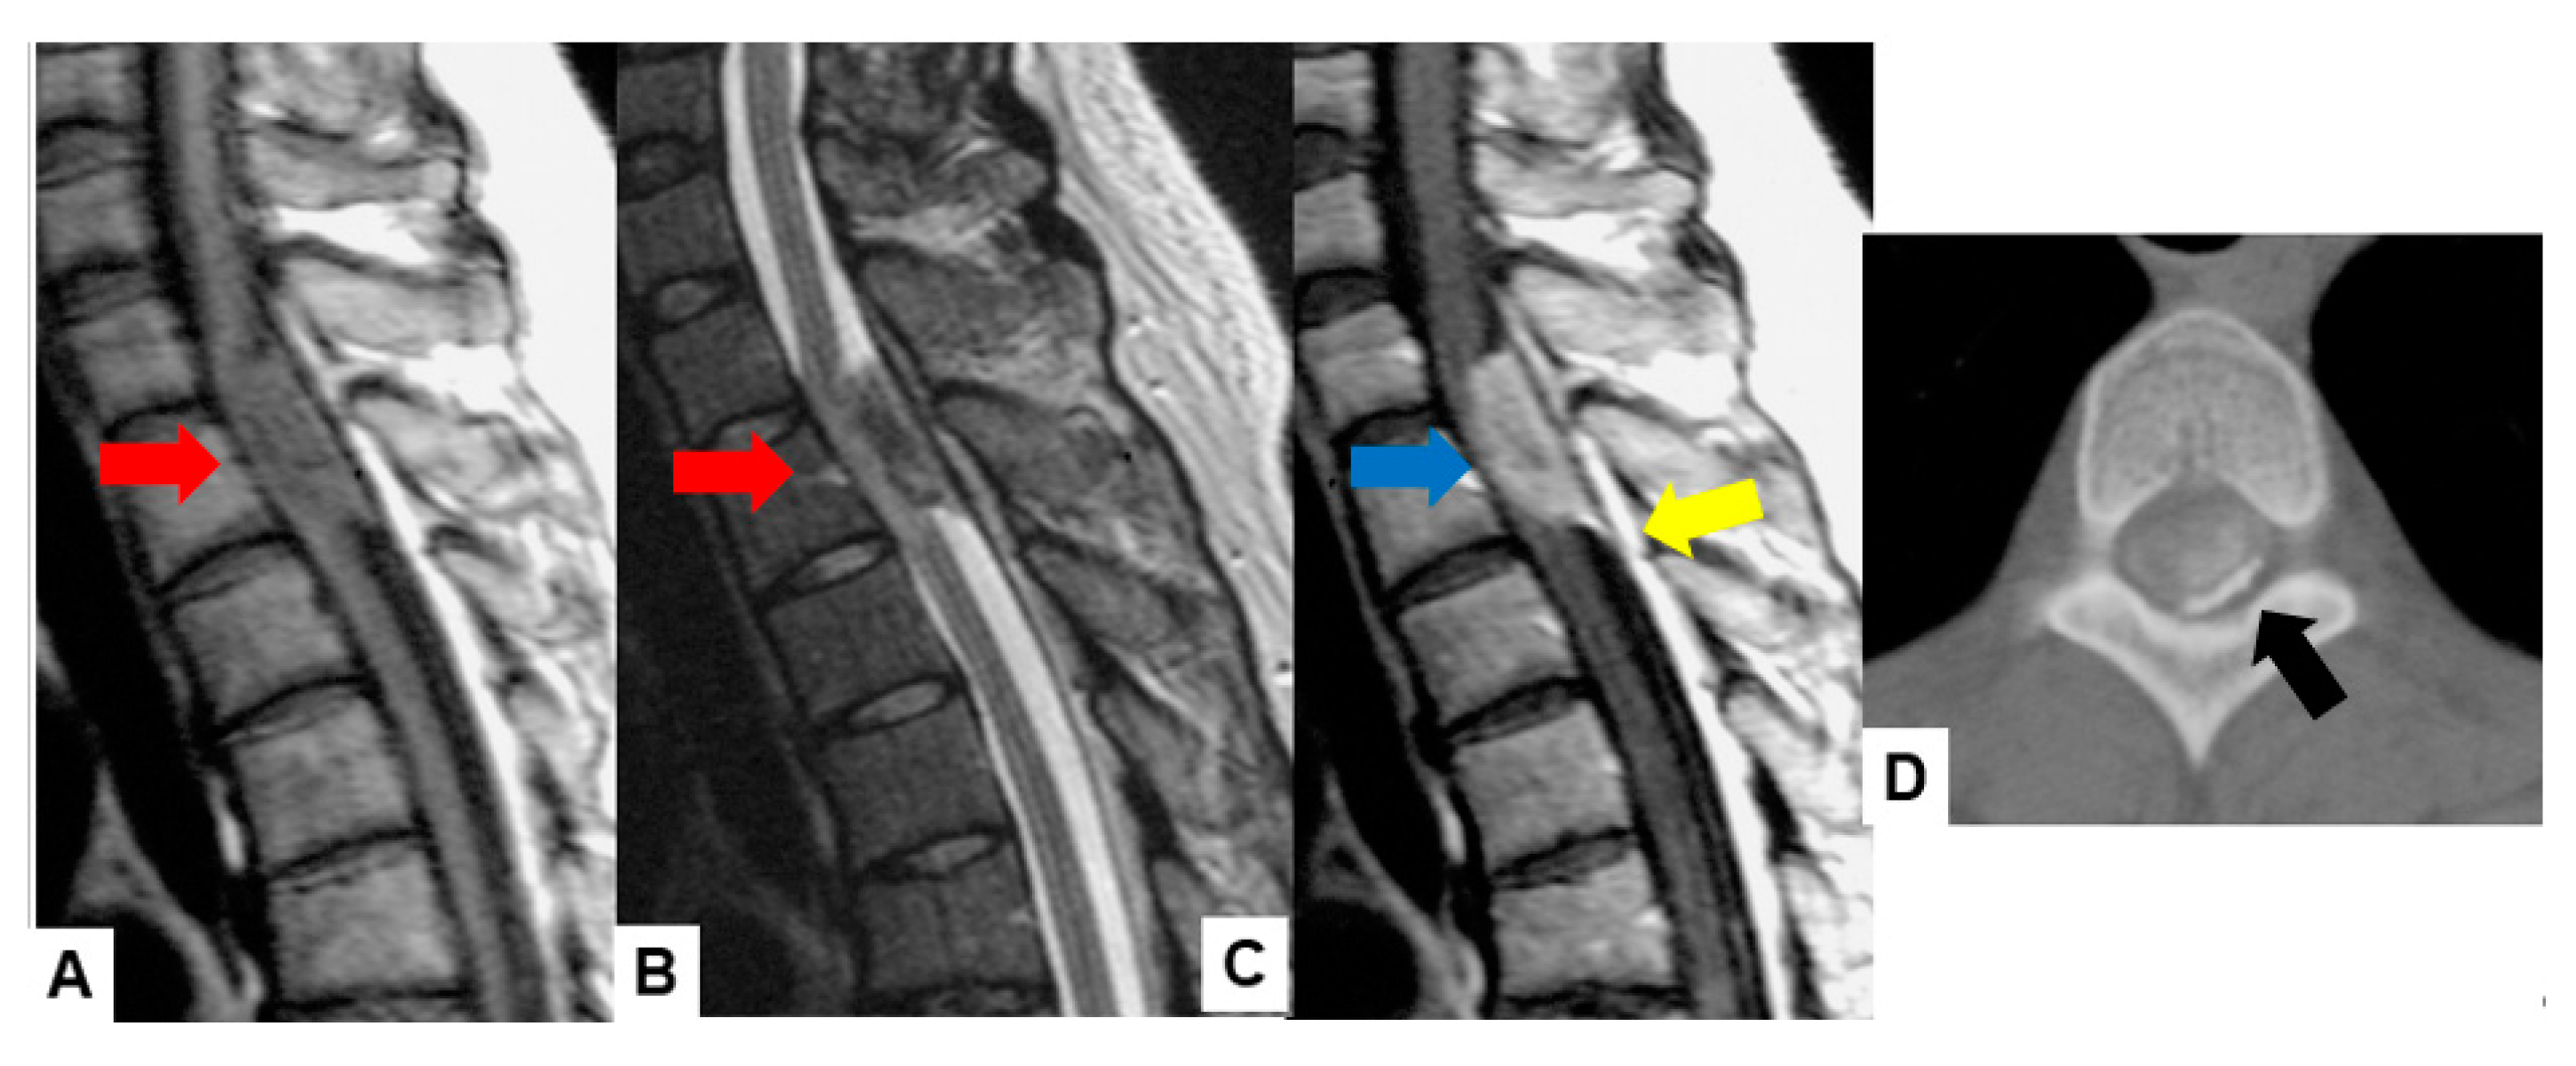

2.1. MRI and CT